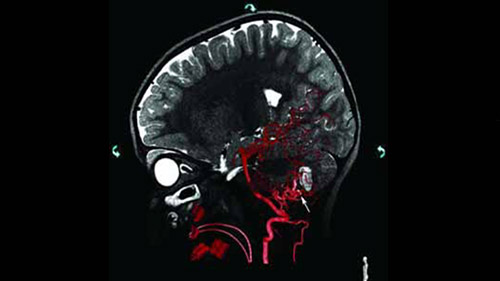

Live 3D MR/CT Roadmap fuses live 2D fluoroscopy on a pre-acquired MR or CT image, which may reveal hidden anomalies and enable real-time motion compensated navigation to support interventional procedures. Live 3D MR/CT Roadmap provides full 3D view for guidance of guidewires, catheters and coils through complex vessel and anatomical structures.

Live 3D Roadmap allows you to follow the advancement of guidewires, catheters and coils in real-time. It automatically adapts in real-time to changes in C-arm angulation and rotation, table movement, field of view and source-image distance.

High-resolution 3D-RA vascular images or previously acquired 3D segmented MRA or CTA data is registered to the current patient position through a low X-ray dose 3D-RA scan, allowing ‘re-use’ of contrast and X-ray doses.